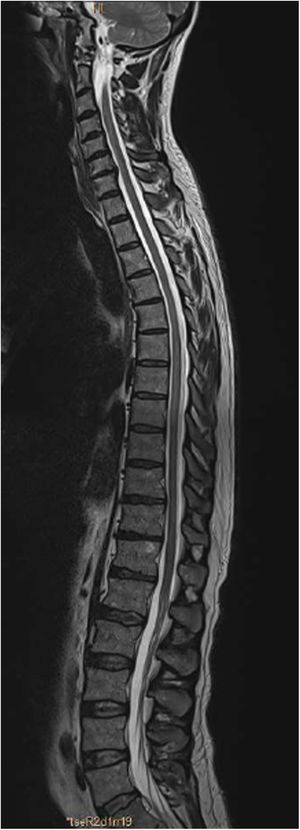

An MRI study (Figs. 1 and 2) revealed a slight signal alteration in the T6-T11 segments, with hyperintensity on T2-weighted sequences; the lesion did not present gadolinium uptake or mass effect. These findings are compatible with longitudinally extensive transverse myelitis of the thoracic spinal cord.